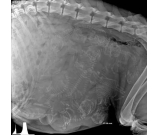

大王搞笑动物怀孕之后照的B超照片,涨姿势了!...